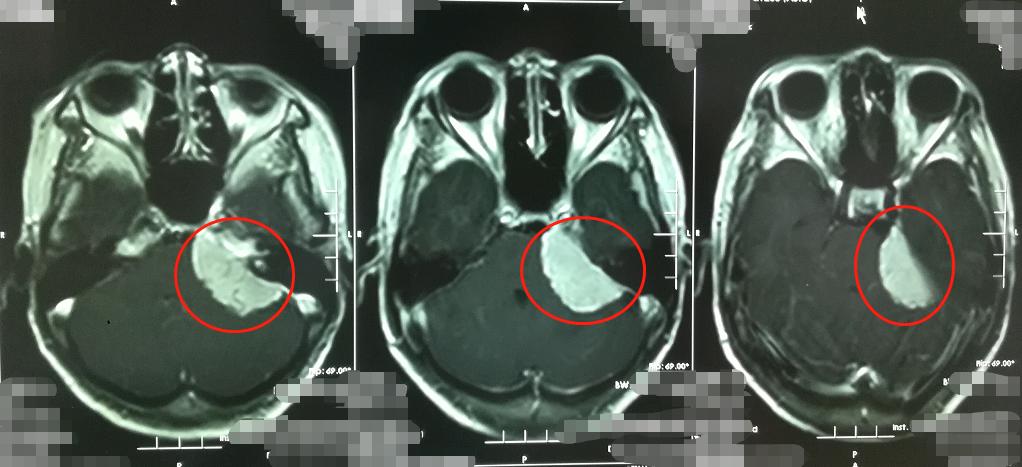

我院接诊的副院长、神经外五科主任鲁明仔细询问患者的症状,结合影像检查,判断为脑膜瘤的可能性较大,大小约为4cmX3cm。

很快,金阿姨接受了肿瘤切除手术。术后病理诊断为良性脑膜瘤,证实了鲁明的术前诊断。